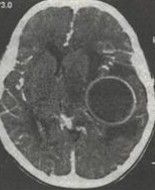

1.新生兒顱內出血CT檢查可證實為顱內出血,可明確顯示出血的類型、位置、形態大小範圍、出血量和對周圍腦組織的壓迫情況;而HIE病理變化包括腦水腫腦組織壞死和顱內出血。這些病理改變可由臨床表現及CT掃描證實

2.頭顱的先天畸形和病毒感染若缺氧缺血發生在出生前幾周或幾個月時,患兒在出生時可無窒息也無神經系統症狀,但在數天或數周后出現亞急性或慢性腦病的表現,臨床上較難與先天性腦畸形或宮內病毒感染相區別。CT檢查可反映頭顱的先天畸形病原學和血清特異抗體檢查有利於病毒感染性疾病的鑑別。